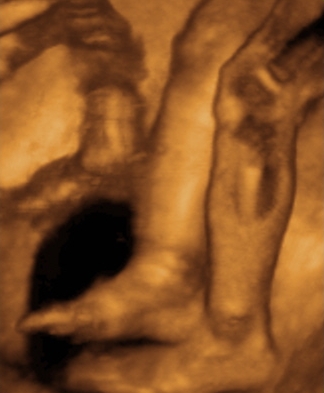

A második képen nyitva van a szeme is